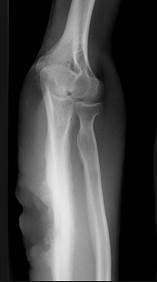

问题 女,35岁,有药物滥用史,右前臂疼痛、肿胀、溃疡,请结合图像,选出最可能的诊断 ( )

选项 A、骨结核 B、骨化性肌炎 C、成骨肉瘤 D、Ewing肉瘤 E、化脓性骨髓炎

答案 E